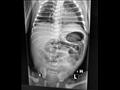

وأوضح رئيس الفريق الطبي أن جرى انتظار استقرار حالة الرضيع بعد الولادة، ثم إجراء الأشعة التي أظهرت وجود انسداد معوي خلقي، أجرى على إثرها جراحة استكشاف عاجلة لإنقاذ الرضيع ليتبين وجود الرتق المعوي مع مسافة كبيرة بين الأمعاء والقولون.